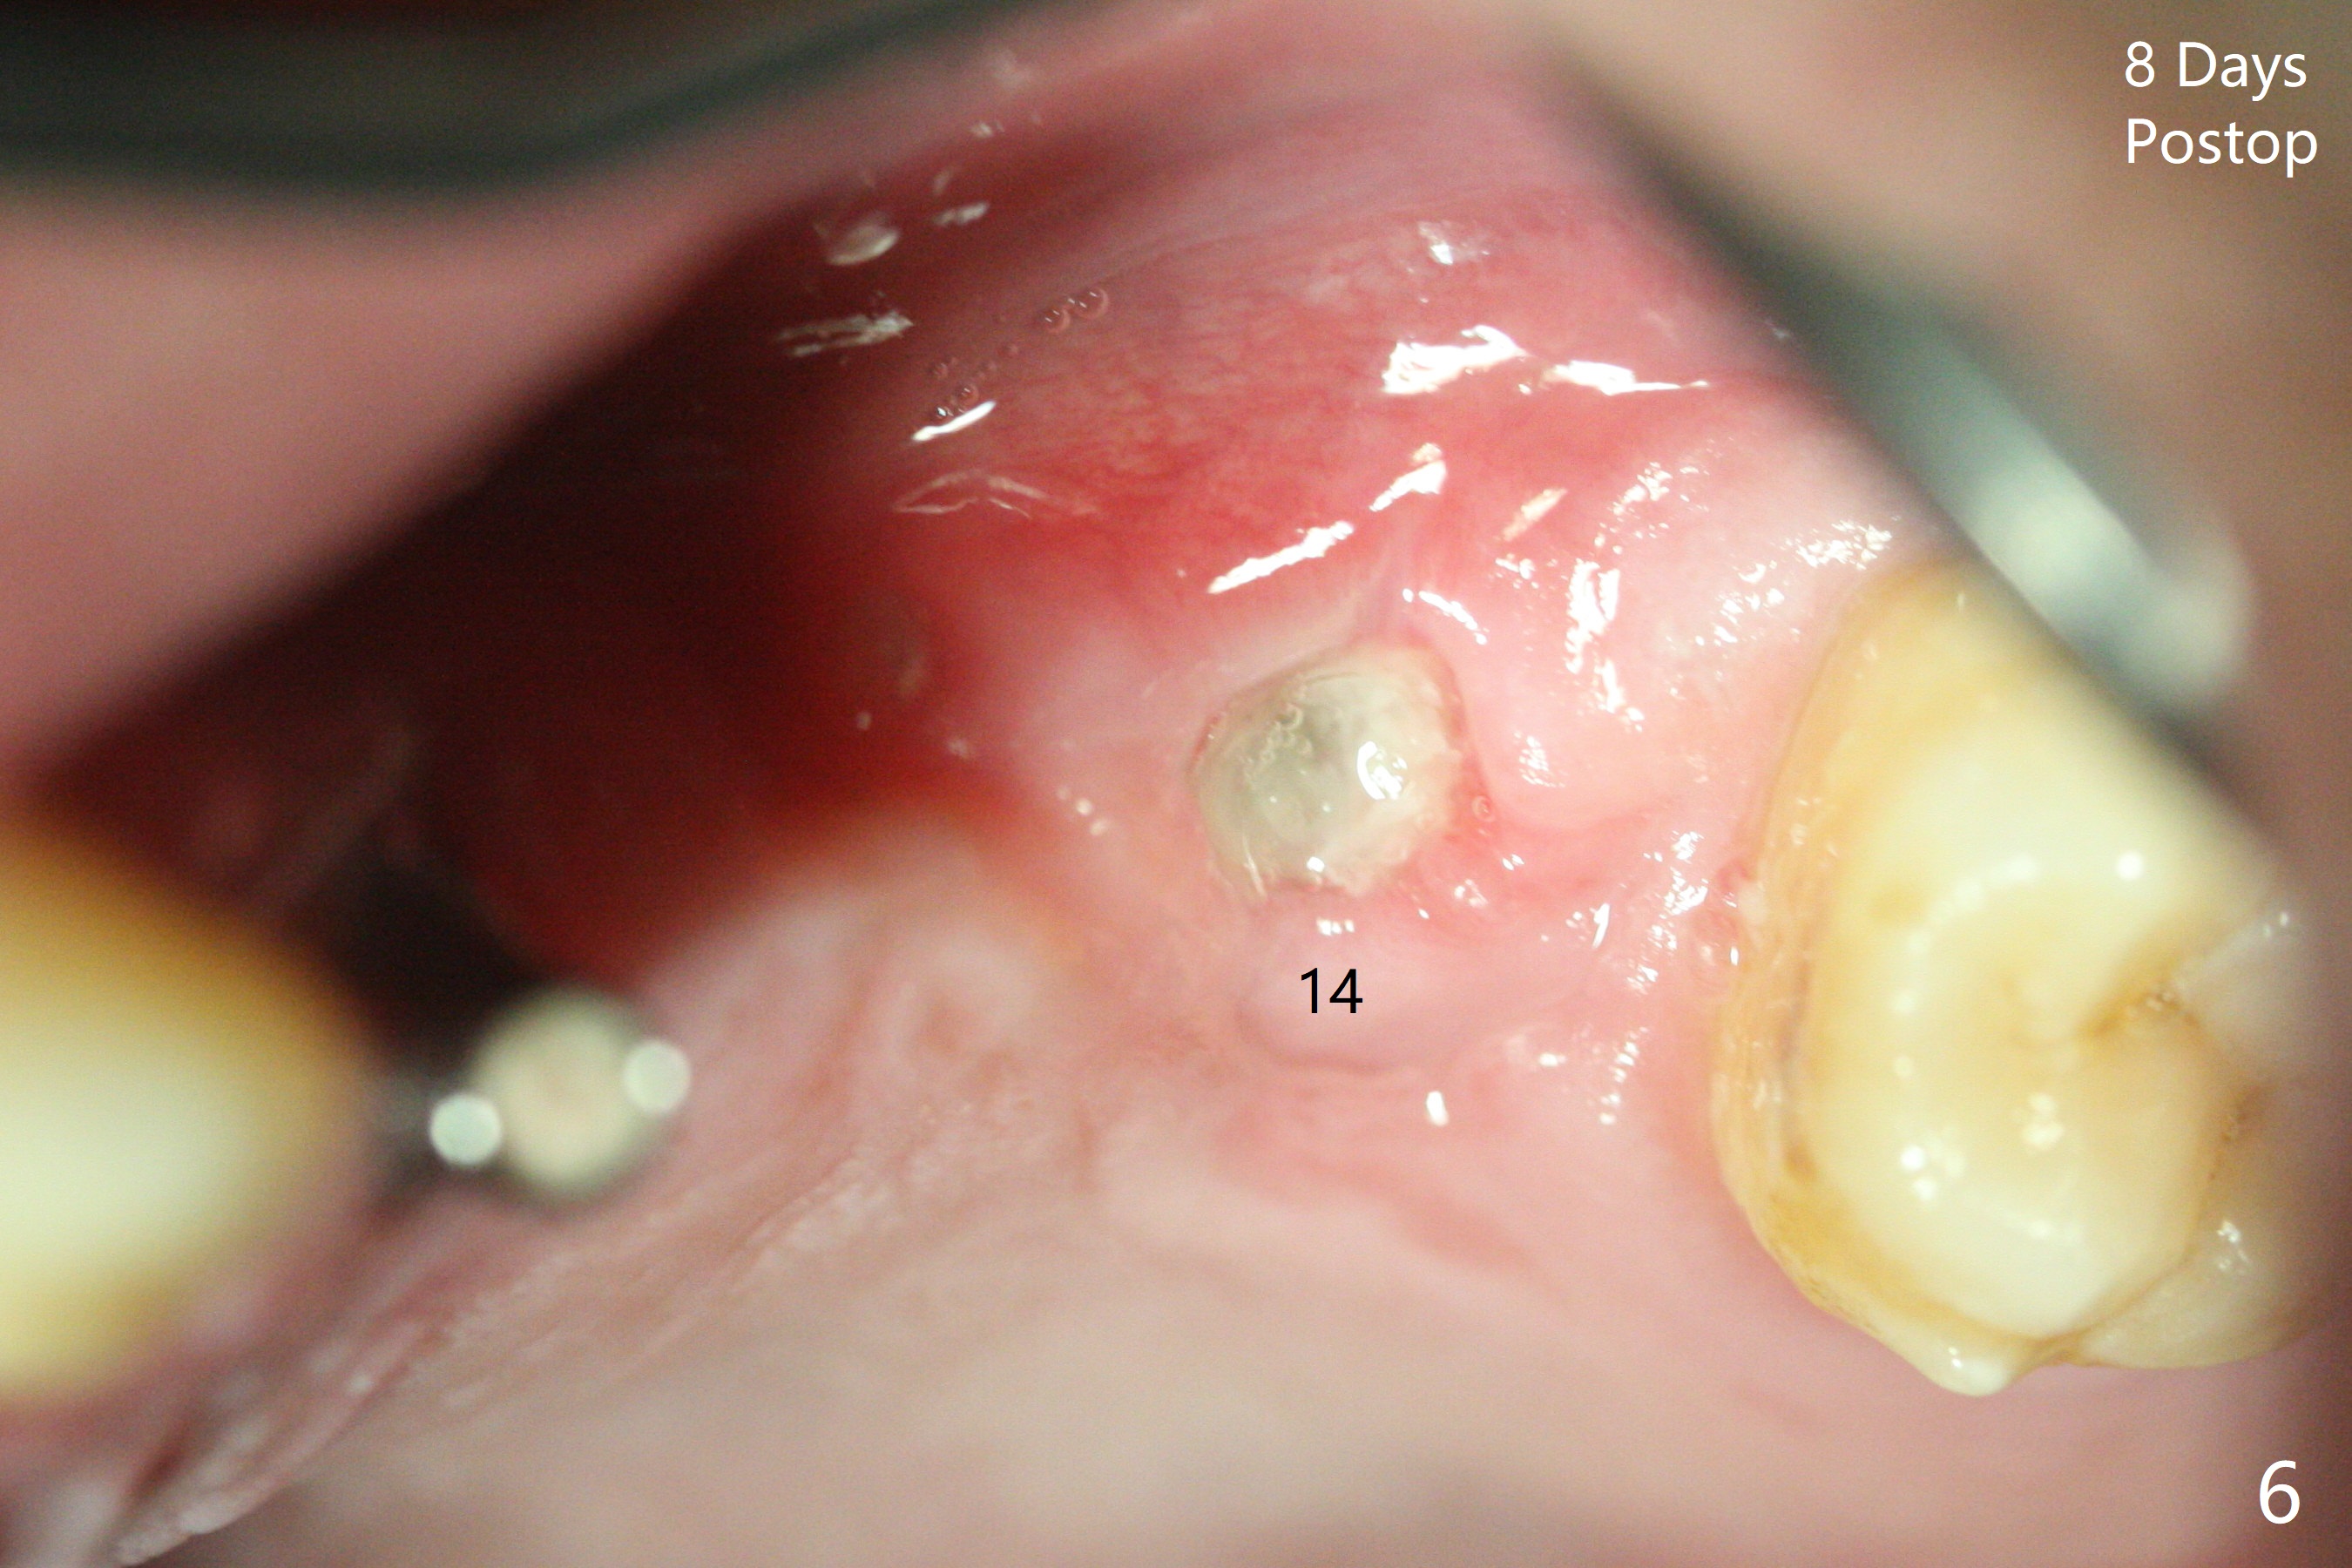

Immediate placement at #12 is smooth with 20 Ncm, whereas delayed one at #14 involves sinus membrane perforation; after insertion of PRF and mixture of autogenous bone and allograft, a shorter dummy implant tries in with stability (Fig.1). The final implant at #14 has ~60 Ncm, but the coronal palatal bone may be insuficient (Fig.2). Sticky bone is placed to bury the implant at #14 (Fig.3 *). After placement (incomplete, Fig.3 <) of a 4.5x7.5(4) mm pair abutment, setting acrylic is applied around the abutment, over the bone graft at #14 (to prevent loss) and pressed into the undercuts of the proximal surfaces of the neighboring teeth for retention (Fig.4). The sockets at #12 heals 8 days postop when a 2nd acrylic dressing dislodges (Fig.5). It appears that the retention of 3-unit acrylic dressing is poor. The wound at #14 also heals, but it would be better to make an incision to save the soft tissue (Fig.6). The bone/implant gap reduces at #13 five months postop (Fig.7 (complete abutment seating)). There is no implant thread exposure at #13 (immediate), while minor exposure mesial to #15 (delayed). The patient complains of food impaction between #13 and 14 buccally 6 months post cementation (Fig.8). Return to Upper Molar Immediate Implant, No Deviation 19 Next Case Xin Wei, DDS, PhD, MS 1st edition 01/21/2020, last revision 02/03/2021